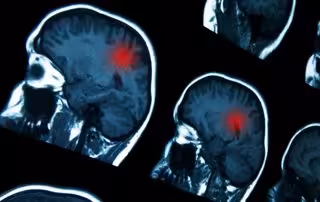

Expertos han recordado que nueve de las 15 patologías más frecuentes en España son neurológicas, siendo el ictus, el Alzheimer, el Parkinson y la Esclerosis Lateral Amiotrófica (ELA) las más frecuentes, por lo que estas patologías son una de las principales causas de discapacidad y mortalidad en España.

En España, 7 millones de ciudadanos padecen algún tipo de enfermedad neurológica, siendo el ictus la segunda causa de mortalidad en el país. El cerebro es uno de los órganos más complejos de nuestro organismo y el encargado de controlar el movimiento, el habla, la memoria, la inteligencia o las emociones, entre otras funciones. El órgano también controla otros aspectos fundamentales como la digestión de la comida o el latido del corazón.